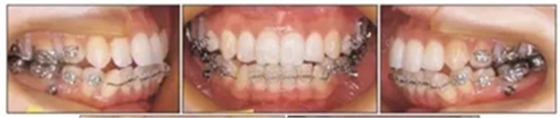

局麻下于植入支抗釘,上頜植入部位在雙側(cè)第二前磨牙和第一磨牙間以及雙側(cè)第一磨牙和第二磨牙間頰側(cè)牙槽骨,下頜植入部位在雙側(cè)第二前磨牙和第一磨牙間間頰側(cè)牙槽骨。植入四周后,用鏈圈連接支抗釘和片斷弓進(jìn)行磨牙壓低。11個月后,覆合從-3.5mm增大到0.5mm (Figure 6)。在此期間沒有出現(xiàn)顳下頜關(guān)節(jié)癥狀。覆合覆蓋分別為0.5mm和3.5mm。頭測分析顯示有下頜骨旋轉(zhuǎn)(FMA, 46.7°to 44.0°)。移除下頜支抗釘和舌弓。